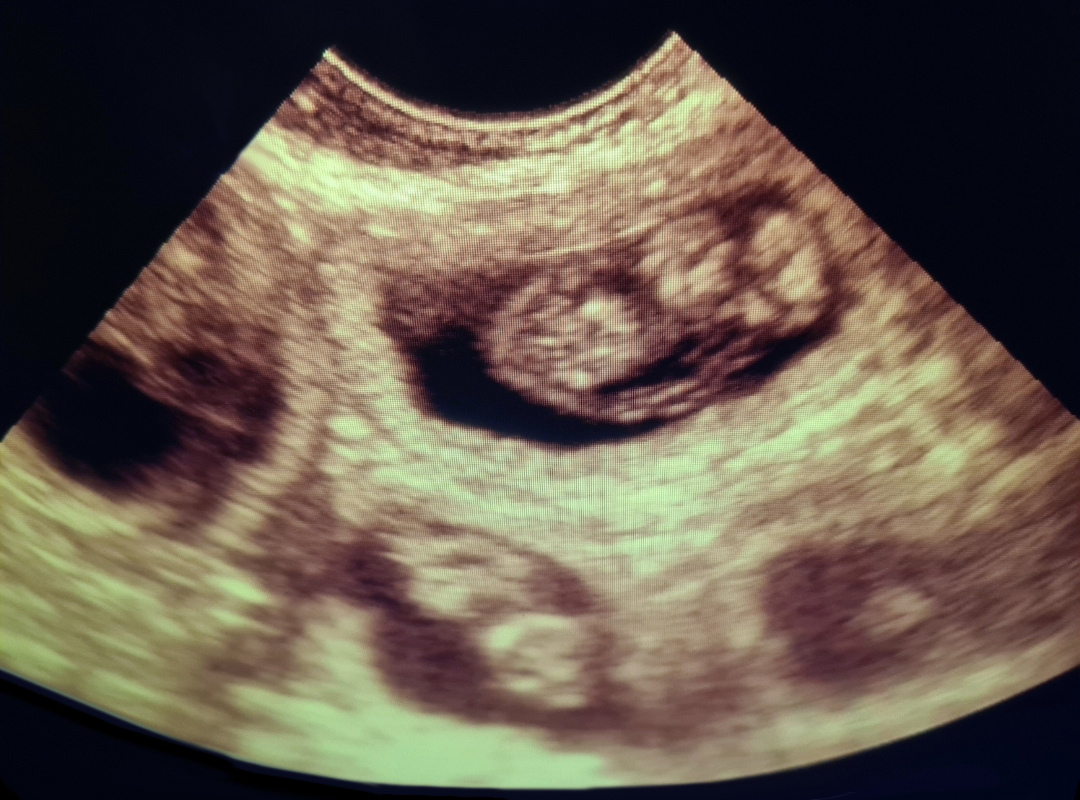

If you believe your pet may be pregnant, we offer gentle and completely painless ultrasound scans to help confirm pregnancy in dogs and cats. These scans can typically be performed from around 28 days after mating.

During the scan, your pet remains calm and comfortable with you gently holding them. A small amount of gel is applied to their abdomen, and a handheld probe is moved carefully over the area to view any developing puppies or kittens.

Using a reliable Scan Pad Ultrasound scanner, Julie can confirm pregnancies and provide you with email copies of any images showing puppies.